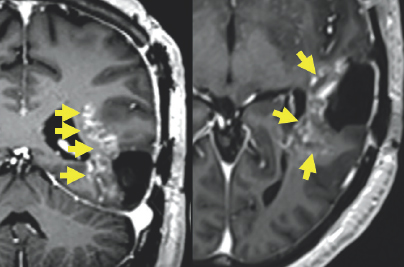

Unfortunately, an MRI scan in October of 2019 revealed worrisome imaging of potential local progression of the tumor (Fig. 2.1–2.3). In addition to this troubling discovery, abnormalities in Columbus’s neuro-cognitive capacity, such as issues with his memory and word-finding capabilities, were gradually becoming more pronounced. This word-finding difficulty showcased itself through his inability to retrieve words for use in regular speech, despite his retention of the ability to understand the English language. To treat these new symptoms, Columbus was put on the steroid dexamethasone.

(Left) Two light gray colored blobs are surrounded by varying dark gray structures. These white blobs have gray spots on them. The first is located in the center of the image and is highlighted by a yellow circle. The other is located towards the right of the image and is highlighted by four small yellow arrows. (Right) A white ribbon-like figure is shown towards the right of the image. It is surrounded by variations of gray color enclosed by a black and white outline.

FIGURE 2.1 Brain MRI before surgery. Axial (left) and coronal (right) post-contrast images show a large mass that appears bright after being injected with IV contrast within the posterior and anterior aspect of the left temporal lobe (yellow arrows and circle), most consistent with high-grade glioma.

Variations of gray color are enclosed by a white outline. In the center of the image, there is a very small white blob highlighted by a red circle. In the top right of the image, there is a white colored blob highlighted by a yellow circle. (Right) Gray colored variations are enclosed by a black and white outline. To the right of the image, there is a significantly large white blob highlighted by a yellow oval.

FIGURE 2.2 Brain MRI before surgery. Additional nodular areas of abnormal enhancement that appear bright after being injected with IV contrast are noted in the anterior temporal lobe (yellow circle) and the left aspect of the midbrain (red circle). There is surrounding signal alteration on the MRI sequence image most consistent with swelling (yellow oval).